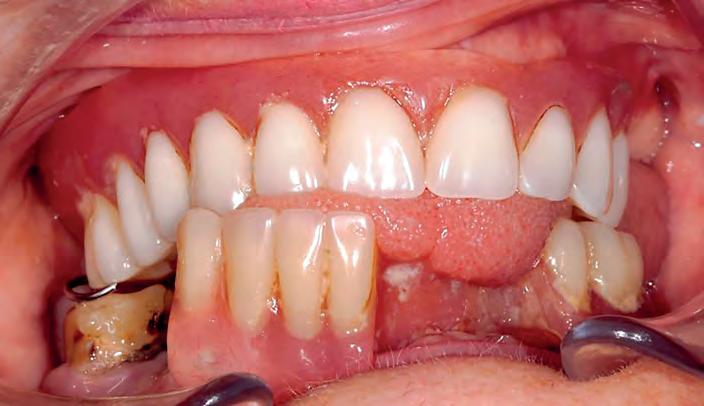

A 58-year-old female patient presented in the dental practice, as she was dissatisfied with both the function and the aesthetics of her current restoration. When chewing, the partial denture (lower jaw) and the full denture (upper jaw) would slip back and forth and did not provide a secure grip. The denture teeth appeared lifeless and the mucogingival areas were smooth and level with an artificial appearance. Following extractions in the lower jaw, region 31 to 34 did not have any restoration, as the partial denture had not been extended. Only tooth 46 was still present, which the patient insisted she wanted to keep. The molar proved worth retaining and showed no clinical or radiological signs of severe periodontal damage. Once the impact of a partial denture on the only remaining tooth (46) had been explained to the patient, it was decided that the new lower denture should be designed so that in the event of tooth loss, a denture tooth could be added by making minimal changes to the design of the denture. The decision was therefore taken to work around tooth 46 during fabrication of both dentures. The patient wanted a new restoration with a natural appearance that offered her peace of mind with a secure grip when chewing and speaking.

After detailed consultation, she decided to have a new full denture made. For this purpose, the VITAPAN EXCELL denture tooth was selected in the appropriate tooth shape to ensure a natural appearance and setup in accordance with aesthetic guidelines. In the posterior area, VITAPAN LINGOFORM was used. As an initial basis for the work to be completed, anatomical situation impressions were taken with alginate in order to create custom trays in the laboratory. These were used in a second session to take mucodynamic impressions. The first impression was taken using Heavy Body, and the second, fine impression using Light Body A-silicone. Once the master model had been fabricated, this was used as a basis for fabricating bite registrations with wax rims for determining jaw relation. The spatial arrangement of the jaws in relation to one another could be transferred to the articulator using the intraorally encoded registration data. Following analysis of the model, the appropriate wax setup for the patient was started.